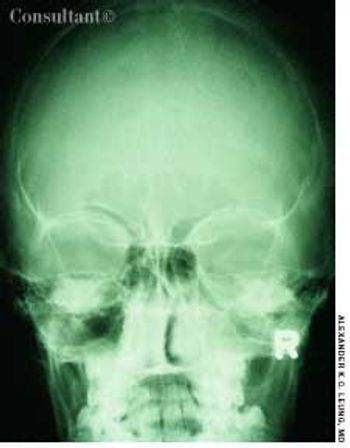

A 74-year-old man, who had been aware of a gradual increase in hat size over the past 3 years, complained of a mild headache and backache. His serum phosphatase level was 1,475 U/L (upper normal limit, 120 U/L). Skull films showed calvarial enlargement caused by thickening of the cortical tables, radiolucency in the frontal and occipital regions, and patchy osteosclerosis that produced a cotton-wool appearance.